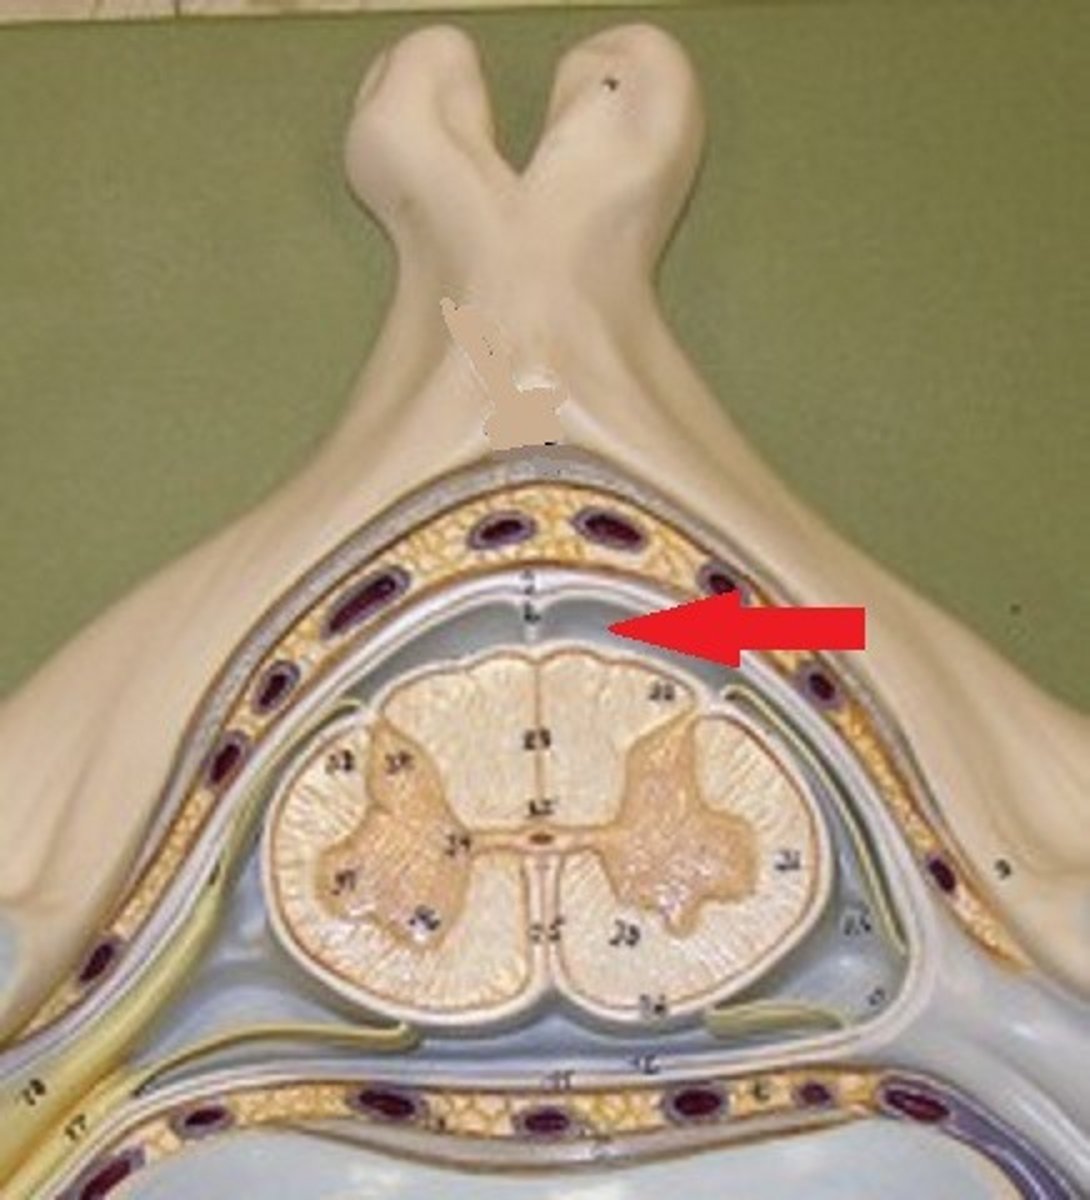

spinal cord structure

white matter of spinal cord

gray matter of spinal cord

posterior gray horn

lateral gray horn

anterior gray horn

posterior white column

lateral white column

anterior white column

central canal of spinal cord

posterior median sulcus

anterior median fissure

Posterior Root

posterior root ganglion

Anterior root

Spinal Nerve